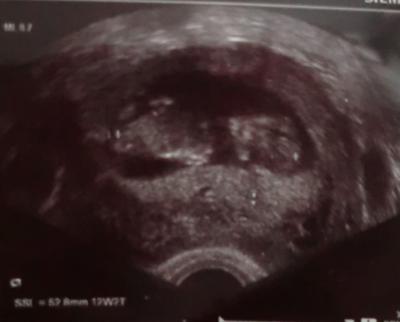

Alles wunderbar! Baby ist jetzt 5,2 cm groß... Laut US berechnung sagt Computer 12+2... Bin aber 11+6 ... Also ich komme mittwochs jetzt immer eine woche weiter ;) Hat sehr dolle rumgeturnt... Arme beine , alles daaa ;) Wahnsinn wie schnell das geht haha ;) Anbei noch ein foto vom Baby ;)

Bild zu Bin zurüüüüüüüüüüück ;) - Forum für März - Mamis